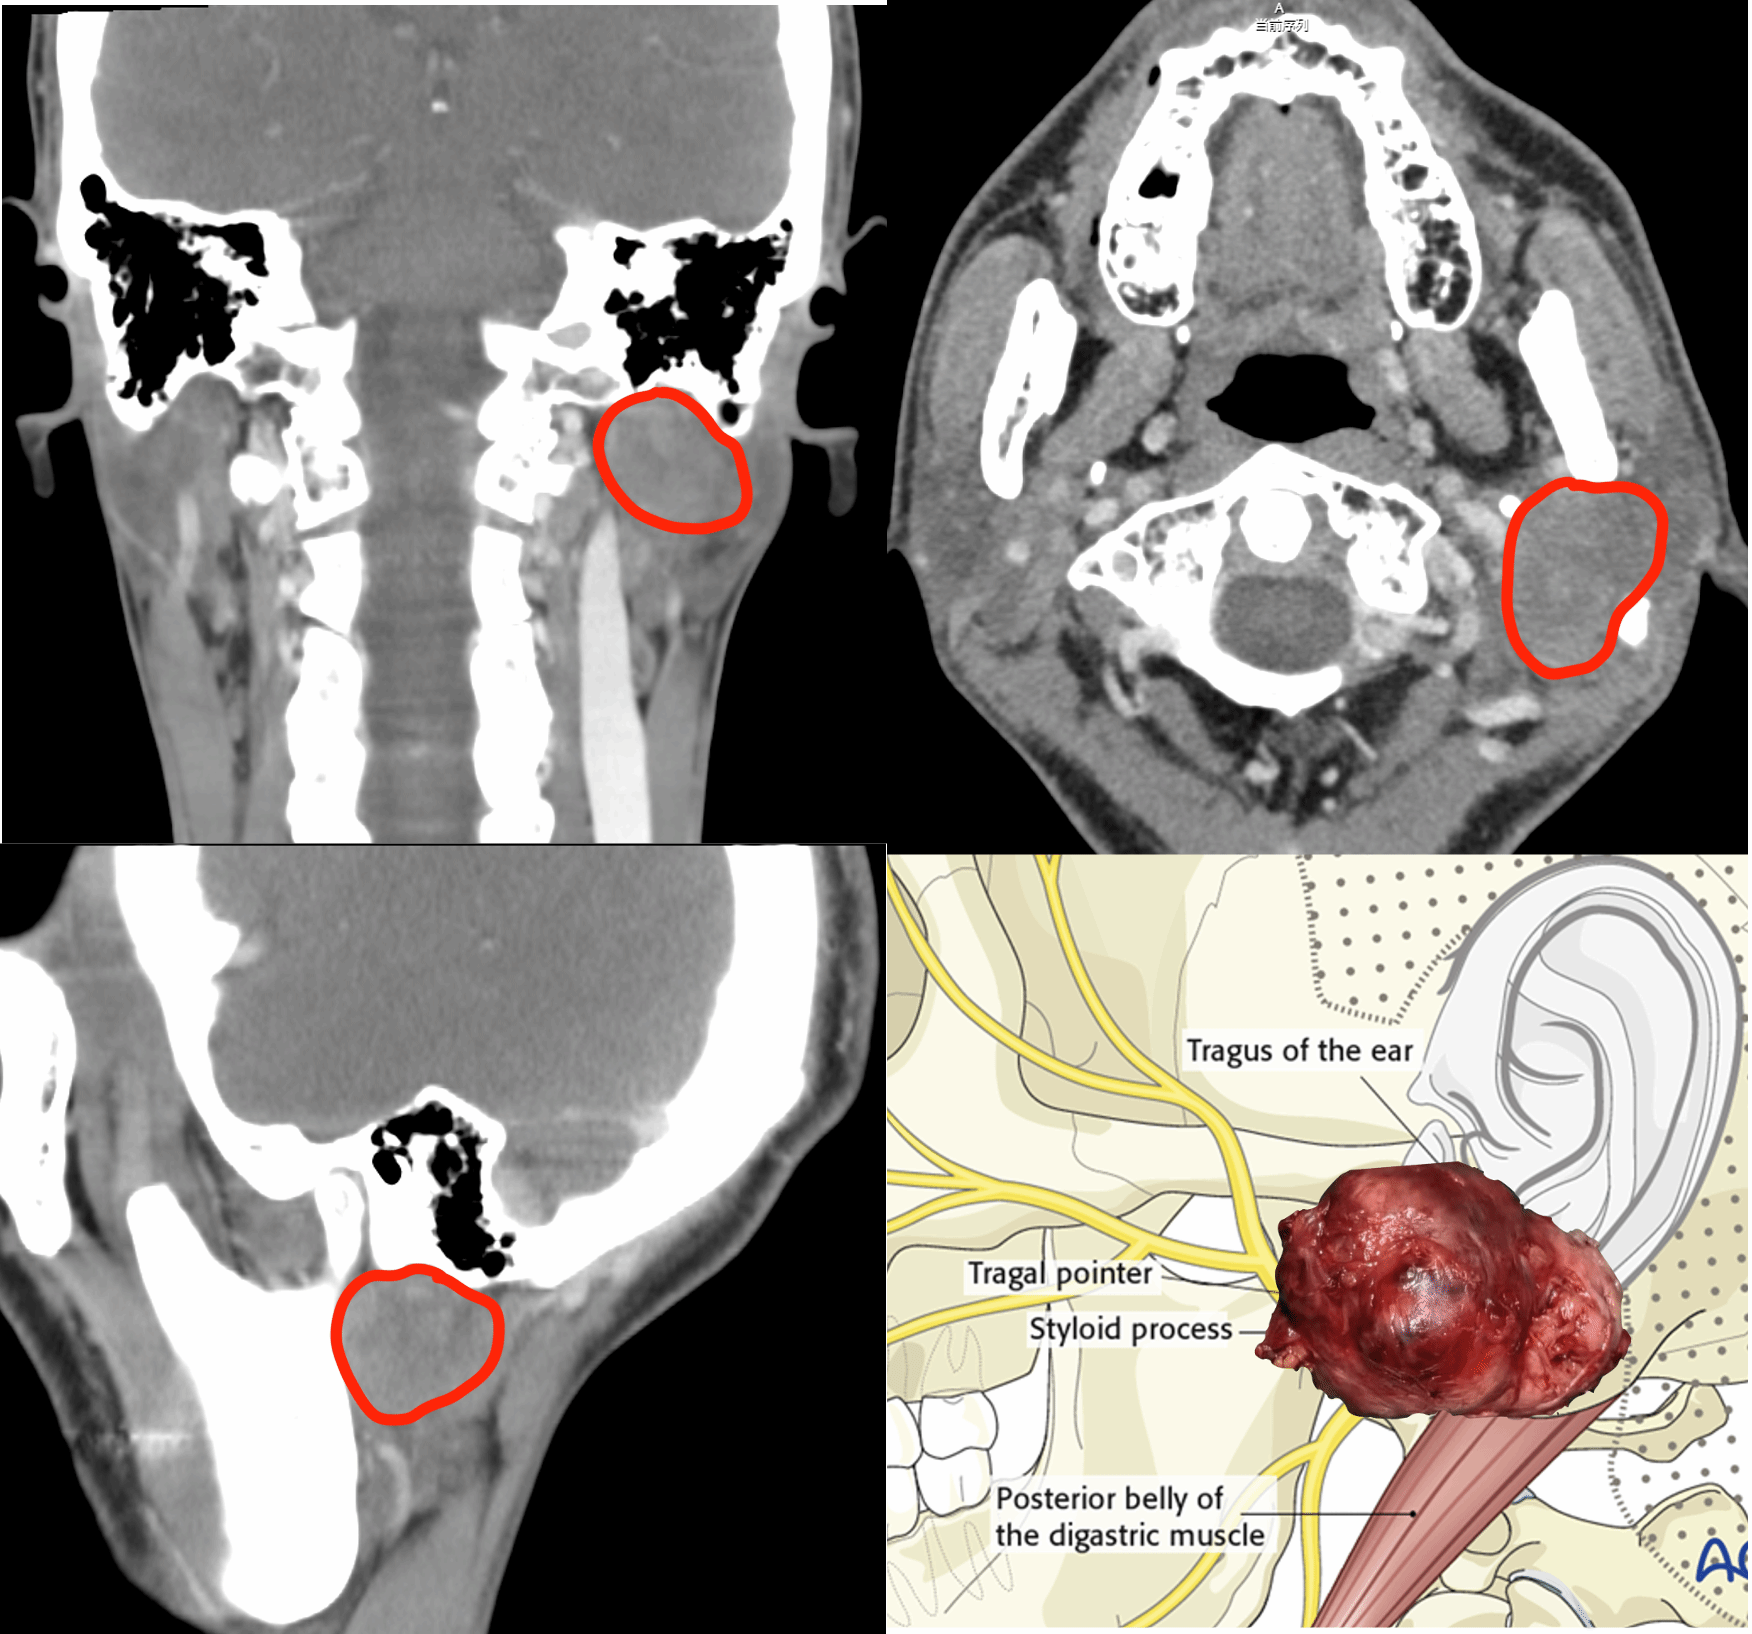

3个月前,徐先生无意中发现左耳后有一个包块,在外院经超声、CT 检查,确诊为左侧腮腺肿瘤。但这枚肿瘤绝非普通腮腺肿瘤,生长位置堪称 “极度凶险”:

●体积大:肿瘤最大直径近 5cm,堪比儿童拳头,大幅增加手术剥离难度;

●位置深:藏匿于乳突尖内侧、面神经主干深面,向上直达侧颅底,常规手术切口难以充分暴露;

●粘连紧:肿瘤与面神经如藤蔓般交织缠绕,术中稍有不慎,就可能导致患者 永久面瘫,出现口角歪斜、无法闭眼等严重后果;

●邻血管:紧贴颈内静脉、颈内动脉,手术如同 “悬崖边起舞”,大血管一旦损伤,极易引发 致命性大出血。

更棘手的是,面神经如一张密网将肿瘤牢牢包裹,肿瘤还突破乳突尖高度,沿茎乳孔深入侧颅底,手术难度呈几何级攀升。面对这一超高难度病例,传统单一术式无法兼顾 “肿瘤完整切除” 与 “神经功能保护”,北医三院耳鼻喉科果断打破亚专业壁垒,以团队协同作战破解难题!